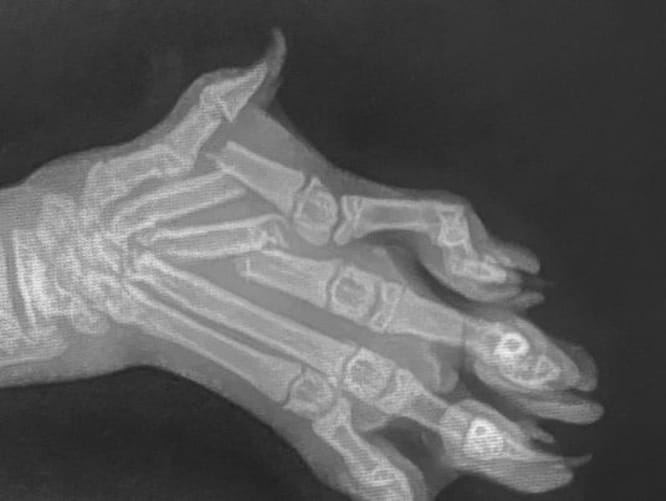

Mukki hat mehrere Verletzungen

Er braucht Operationen und muss unter Aufsicht sein. Um ihm diese zu ermöglichen brauchen wir deine Unterstützung.